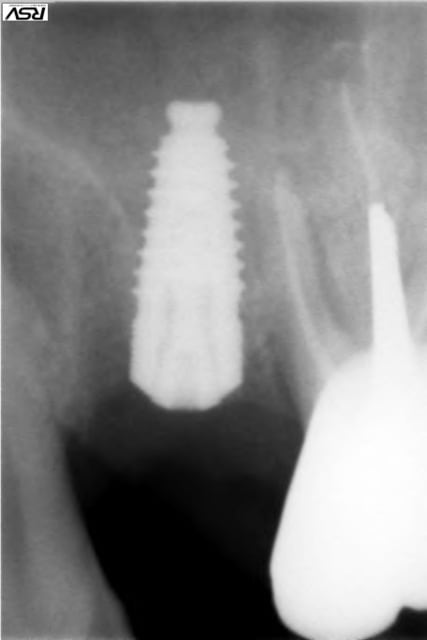

Présentation du cas : extraction de 26 , attente 2 mois cicatrisation, hauteur résiduelle estimé à 5 mm , mauvaise surprise après avoir oté le provisoire, très belle crète bien large mais invaginée en son centre.

Forage au milieu à 3mm + effraction du plancher ,manoeuvre de Walsava OK, bourrage au Gen Oss (0.5cc) , re Walsava, et implant IDCAM 10/5.2 bloqué au maximum .

oups , les photos de ce matin.

sur la radio post-op, l'espace entre l'implant et la pré-molaire, non comblé, ne causera pas de problème ?

J'aurais tenter un SA-3, pour comblé plus large et évité ce vide, qui est un ramasse bactérie dans le sinus...

pour céramik

peut être , mais je parie plutot sur une remontée générale du plancher dans ce secteur, vu la faible distance avec la prémolaire.

Tiens jette un coup d'oeil sur la partie mésial de cet implant sans comblement où 3 spires ont été englouties dans la cicatrisation osseuse